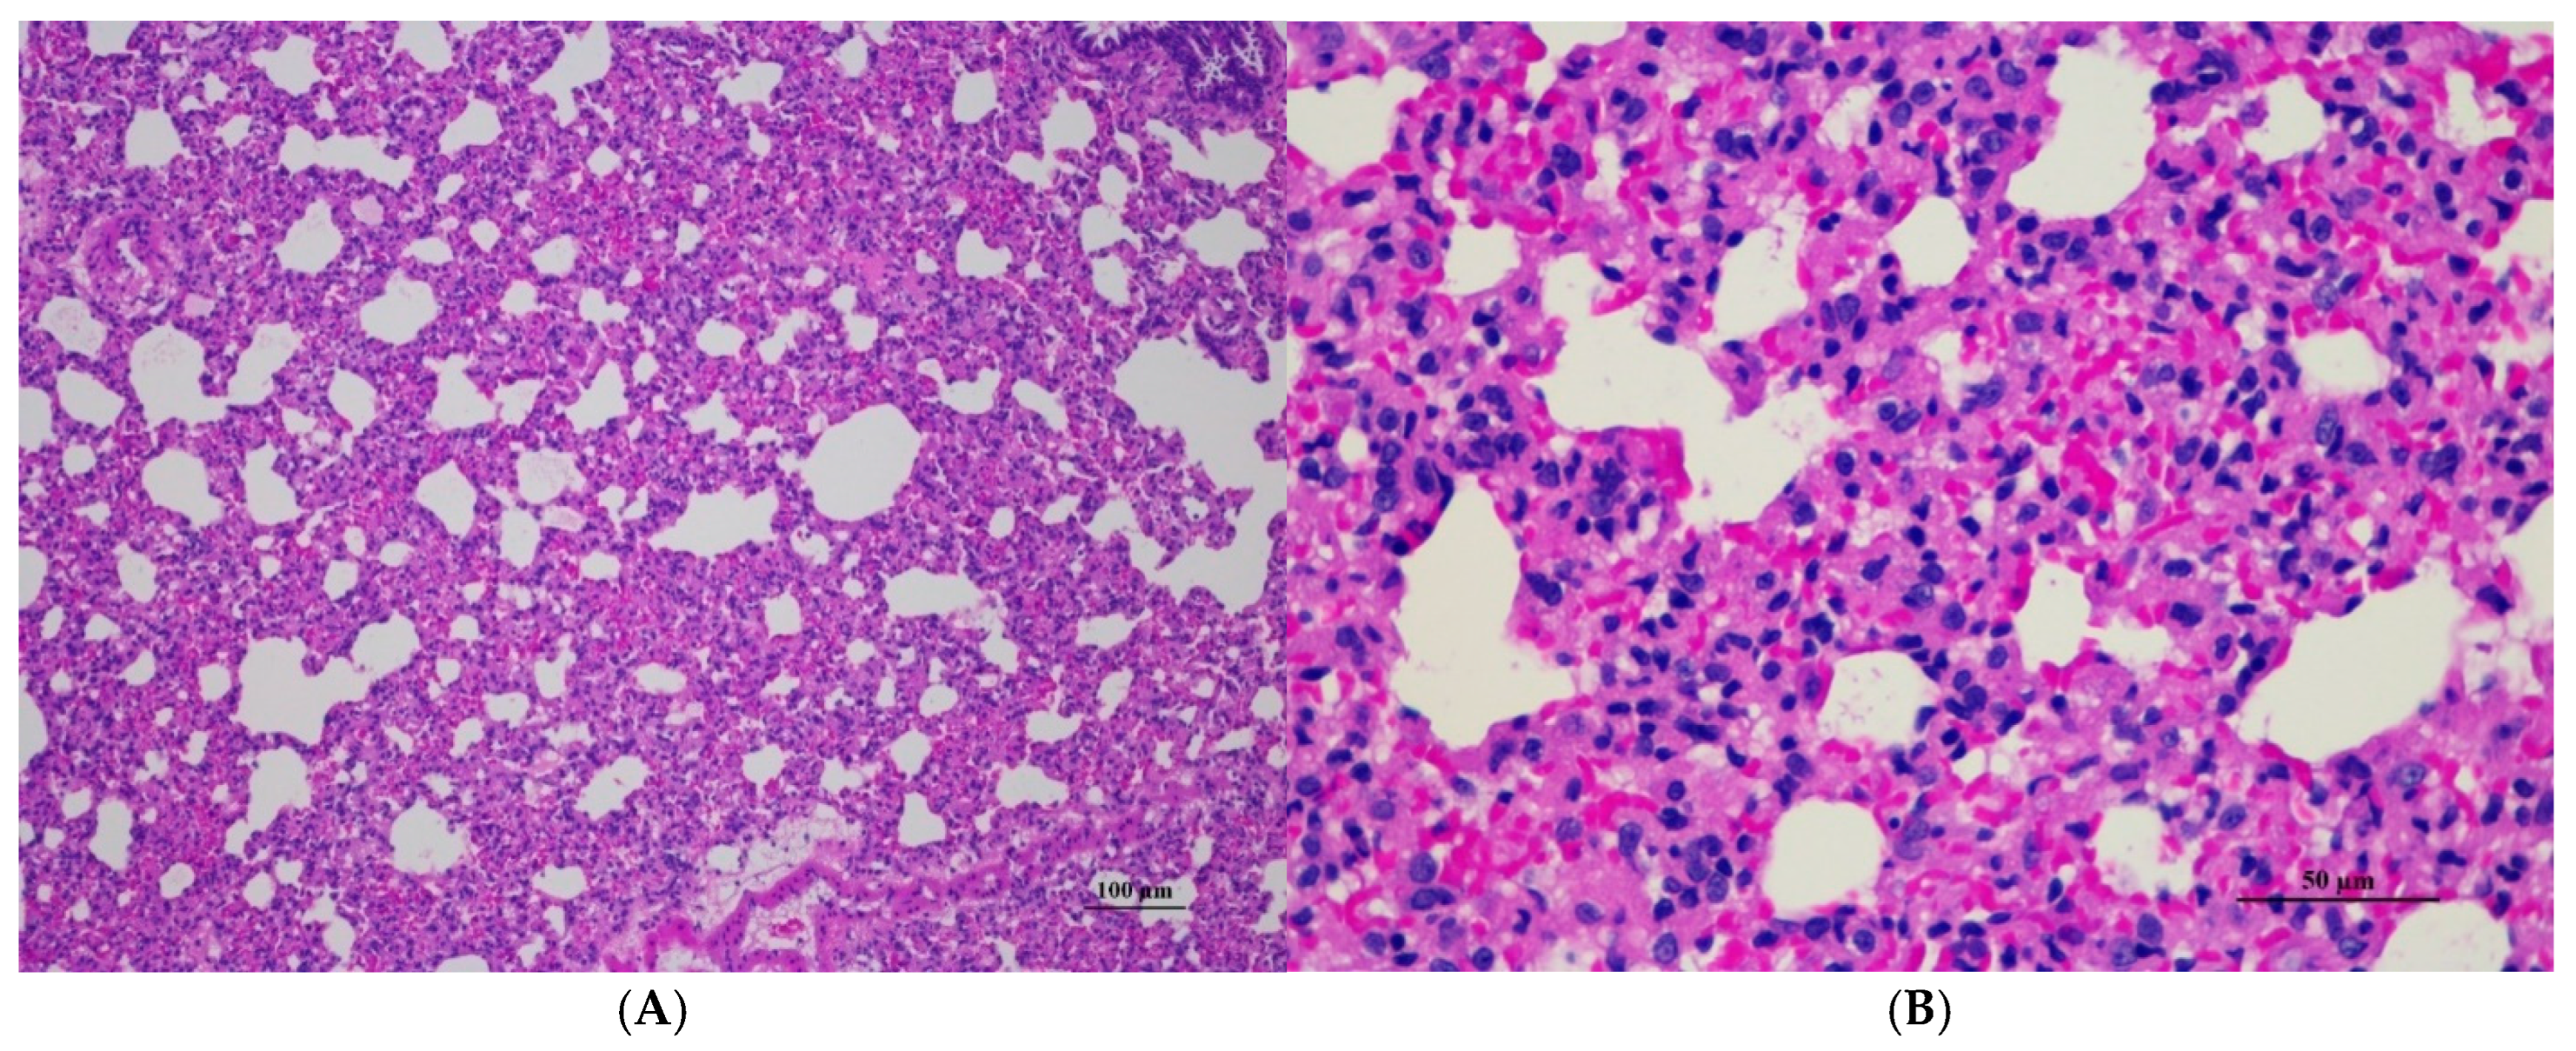

Figure 10.

Histopathological examination of rat lung tissue in sub-acute toxicity from daily (28 days) fed oral dose of CDF showed histopathological alterations. (A) Pulmonary parenchyma reveals prominent thickening of alveolar septa with infiltration of inflammatory cells (100×, H&E). (B) High magnification showed alveolar septa infiltrated by numerous mononuclear cells. Capillary engorgement and focal hemorrhage were observed (400×, H&E).

Histopathological analysis of rat organs following 28-day cassava fiber administration revealed mild hepatocellular swelling and vacuolation in the liver, deemed within normal limits, while the kidneys, heart, and spleen exhibited no significant lesions; however, the lungs consistently displayed moderate to severe alveolar edema, septal engorgement, hemorrhage, and inflammatory cell infiltration, suggesting a potential pulmonary response to the cassava fiber, despite the absence of overt clinical toxicity.

Abnormalities were found in the lung tissue of both sexes, i.e., interstitial pneumonitis. The histopathologic feature of the lungs shows varying severity degrees of alveolar edema, alveolar septal engorgement, alveolar hemorrhage, and inflammatory cell infiltration to pulmonary parenchyma in all groups. Normal lung tissue, except for alveolar septal thickness and alveolar hyperemia, was found in both satellite groups. This abnormality may indicate infection from the facility used for laboratory animals. However, further investigation is required.